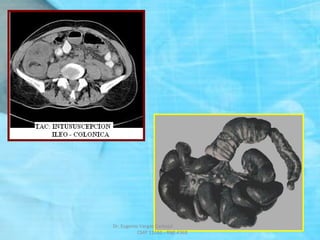

TAC: INVAGINACION – INTUSUSCEPCION

SIGNO DE “SALCHICHA”

SIGNO DEL “TIRO AL BLANCO”